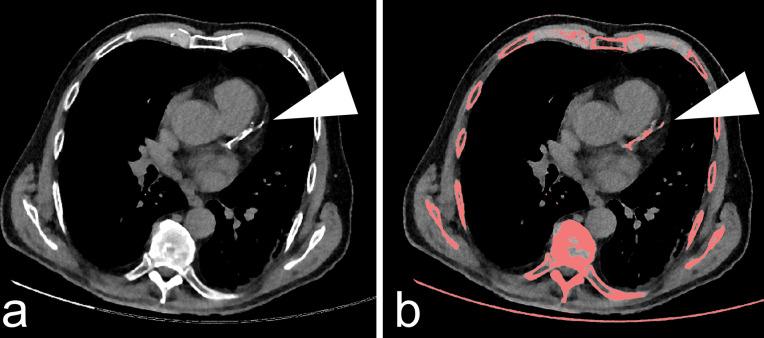

Cardiovascular comorbidity anticipates severe progression of COVID-19 and becomes evident by coronary artery calcification (CAC) on low-dose chest computed tomography (LDCT). The purpose of this study was to predict a patient's obligation of intensive care treatment by evaluating the coronary calcium burden on the initial diagnostic LDCT.

CAC scoring on LDCT might help to predict future obligation of intensive care treatment at the day of patient admission to the hospital.

心血管合并症预示着COVID-19的严重进展,并通过低剂量胸部计算机断层扫描(LDCT)上的冠状动脉钙化(CAC)得以显现。本研究的目的是通过评估初始诊断性LDCT上的冠状动脉钙化负荷来预测患者接受重症监护治疗的必要性。

LDCT上的CAC评分可能有助于在患者入院当天预测未来接受重症监护治疗的必要性。